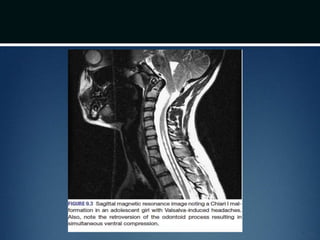

Chiari I Malformation

โ€ข Theory: Difficulty in rapidly equilibriating the CSF

pressure wave seen during the Valsalva maneuver

โ€ข Prolonged intracranial hypertension relative to

intraspinal compartment ๏ƒ  downward migration of

the cerebellar tonsils ๏ƒ  obstruction of normal CSF

flow from 4th ventricle to cervical subarachnoid

space ๏ƒ  CIM

โ€ข Obstruction of Foramen of Magendie by

arachnoid veils or septation might also lead to the

same

โ€ข Non radicular occipital or cervical pain

โ€ข Dysesthesias in the C2 dermatome

โ€ข Neckpain and headache - exacerbated on

exertion or by coughing or sneezing (valsalva

induced)

Diagnosis

โ€ข MRI โ€“ Craniovertebral junction and entire

spinal cord

โ€ข 50-75% patients have syringomyeliasyrinx

โ€ข Symptomatic ventral compression out

of proportion to dorsal compression

๏ƒ  ventral decompression (transoral

odontoid resection)